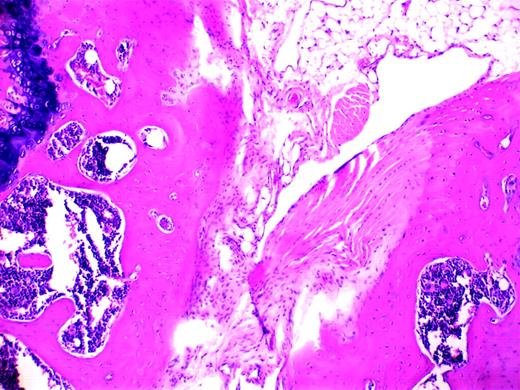

Blood-induced synovitis as a murine model of human HS. See the complete figure in the article beginning on page 2060.

Hemophilic arthropathy is characterized by synovial/endothelial cell proliferation and inflammation, though it is unclear which process is of greater importance or whether they are linked. Deep fenestrations of synovial tissue develop that remarkably resemble sea anemone and, important to this discussion, malignant tissue. Iron has long been recognized as a potential culprit in this altered pathobiology. Morris and colleagues1 first suggested this association after describing iron deposits deep in the synovial layers. More recent studies have linked iron to both the interleukin-driven inflammatory responses involving interleukin 1 (IL-1), IL-6, and tumor necrosis factor (TNF)2 and to c-myc oncogene-mediated cellular proliferation.3